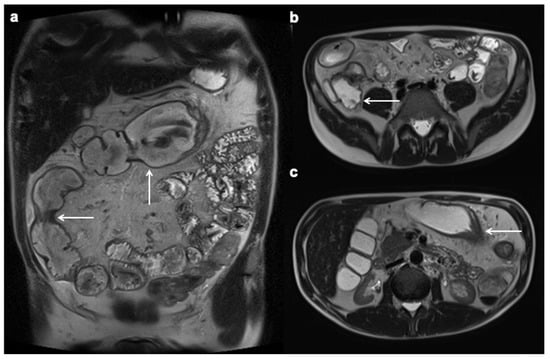

12. Imaging Findings Associated with Non-Active CD Inflammation

- Latella, G.; Sferra, R.; Speca, S.; Vetuschi, A.; Gaudio, E. Can we prevent, reduce or reverse intestinal fibrosis in IBD? Eur. Rev. Med. Pharmacol. Sci. 2013, 17, 1283–1304. [Google Scholar]

- Foti, P.; Travali, M.; Farina, R.; Palmucci, S.; Coronella, M.; Spatola, C.; Puzzo, L.; Garro, R.; Inserra, G.; Riguccio, G.; et al. Can Conventional and Diffusion-Weighted MR Enterography Biomarkers Differentiate Inflammatory from Fibrotic Strictures in Crohn’s Disease? Medicina 2021, 57, 265. [Google Scholar] [CrossRef] [PubMed]

- Tielbeek, J.A.W.; Ziech, M.L.W.; Li, Z.; Lavini, C.; Bipat, S.; Bemelman, W.A.; Roelofs, J.J.T.H.; Ponsioen, C.Y.; Vos, F.M.; Stoker, J. Evaluation of conventional, dynamic contrast enhanced and diffusion weighted MRI for quantitative Crohn’s disease assessment with histopathology of surgical specimens. Eur. Radiol. 2013, 24, 619–629. [Google Scholar] [CrossRef]

- Barkmeier, D.T.; Dillman, J.R.; Al-Hawary, M.; Heider, A.; Davenport, M.S.; Smith, E.A.; Adler, J. MR enterography–histology comparison in resected pediatric small bowel Crohn disease strictures: Can imaging predict fibrosis? Pediatr. Radiol. 2015, 46, 498–507. [Google Scholar] [CrossRef] [PubMed]